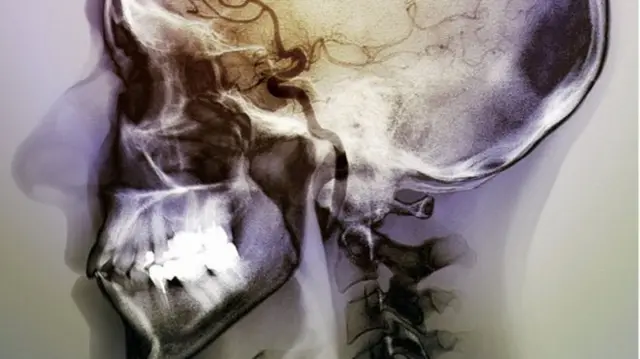

Beynin sigara tiryakiliğiyle bağlantılı kısmı bulundu

Felç sonucu beynin iç kısmındaki insular korteks bölgesi zarar görenlerin sigarayı daha kolay bıraktığını tespit eden uzmanlar, beynin belirli bir bölgesinin sigara tiryakiliğinde itici güç olduğu sonucuna vardı.

Beynin derinliklerinde iyi korunan bir bölgede olan insularr korteks, beynin diğer bölgeleriyle yoğun bağlantılara sahip. Uzmanlar bu bölgenin arzular ve duygularla ilgili olduğuna inanıyor.